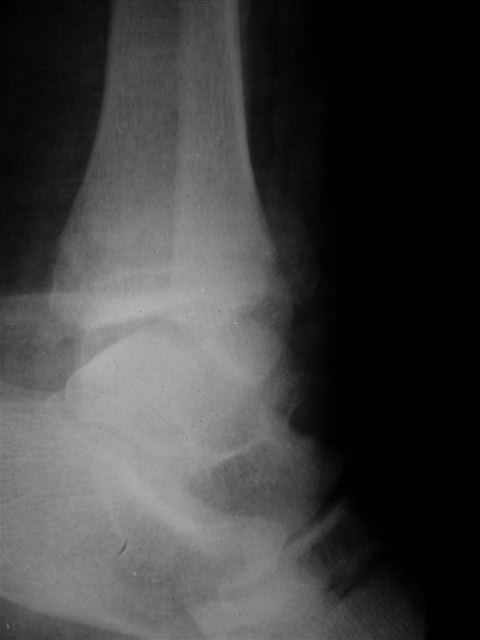

Я предупреждал, что ничего сверхъестественного. Каюсь, что одна из спиц прошла несколько дальше, чем нужно было, но главное - перелом стабилизирован и больной работает суставом в полном объёме, несмотря на представленную раннее травму коленного сустава.

Евгений И Чекашкин